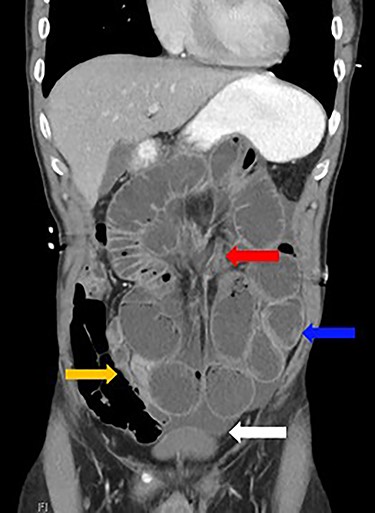

A 52-year-old man presented with a 1-day history of generalized abdominal pain, distension and vomiting. Two years prior, he underwent a subtotal colectomy for colorectal cancer associated with Lynch syndrome and adjuvant chemotherapy. He was haemodynamically stable on presentation. Examination revealed a soft abdomen with marked distension and left periumbilical tenderness, however, no peritonism. Biochemistry showed lactate: 1.9, white cell count: 17 and C-reactive protein: 10. Computed tomography (CT) abdomen demonstrated a closed-loop SBO with transition point mid-abdomen, free fluid but no free gas (Figs 1 and 2). The patient was resuscitated with intravenous fluids, a nasogastric tube was inserted and they proceeded to an exploratory laparotomy for the closed-loop SBO. Intra-operative findings noted a loop of distended small bowel adherent to the anterior abdominal and pelvis side walls, with a loop of ileum twisted at the mesentery secondary to a band adhesion causing the closed-loop obstruction. The patient underwent adhesiolysis and untwisting of the mesentery, which demonstrated viable ileum with no evidence of perforation. In addition, the liver was smooth, there was no evidence of peritoneal metastases and the previous side-to-side ileo-sigmoid anastomosis was intact with no evidence of stricture or cancer recurrence. Lastly, milky intra-abdominal fluid was noted intra-operatively, with a sample sent for biochemistry showing a triglyceride level of 1584 mg/dl indicative of CA. Post-operative recovery was delayed by a prolonged ileus for which they were commenced on total parenteral nutrition (TPN) and slowly upgraded to a low-fat diet following resolution of the ileus. They were discharged home on Day 49 post-operatively.

Dilated loops of small bowel (blue arrow), oedematous mesentery (suggestive of closed-loop obstruction; red arrow), free fluid (evidence of CA; white arrow) and collapsed small bowel (orange arrow)